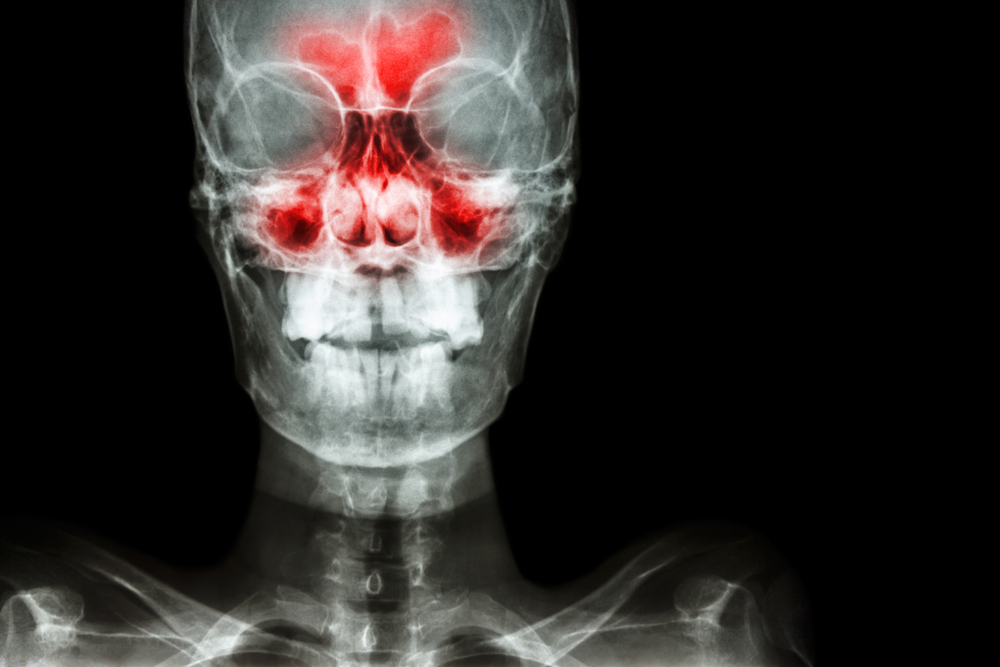

Рентгенологическое исследование используется для диагностики воспаления пазух носа, их опухолей и травм. Также оно необходимо для оценки результатов проведенного лечения.

На рентгенограмме околоносовых пазух видны такие анатомические элементы:

- носовая полость в виде просветления треугольной формы, разделенного перегородкой на симметричные половины;

- в каждой половине носовой полости видны тени носовых раковин, а между ними – просветления, соответствующие носовым ходам;

- с обеих сторон от носовой полости видны треугольные просветления с четкими границами – верхнечелюстные пазухи;

- в пространстве между глазницами видна полость решетчатой пазухи, разделенная тонкими стенками на несколько клеток;

- над глазницами в глубине кости определяются лобные пазухи, они могут иметь разную форму, иногда их разделяют костные перегородки.

При заболеваниях пазух врач может увидеть:

- признаки острого воспаления: слизистая утолщена, в полости пазухи виден горизонтальный уровень жидкости, при нагноении граница содержимого может располагаться косо или быть вогнутой, однако это не обязательный признак;

- признаки хронического воспаления: значительное утолщение стенок, сужение просвета пазухи вплоть до его полного исчезновения (отсутствия пневматизации);